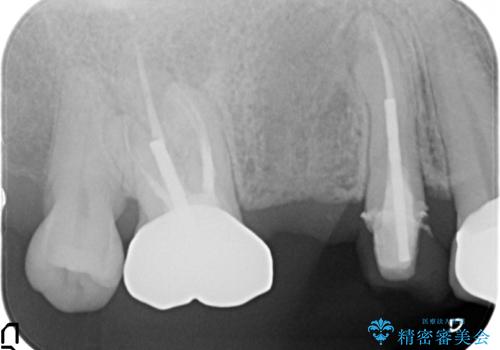

- アメリカの歯科医院にて治療途中の歯の仮歯が割れてしまったので診て欲しいといらっしゃった方の症例です。

しばらくアメリカに戻れそうにないため、当院での治療を希望。土台の築造まで処置は終わっているとのことだったのでオールセラミッククラウンによる補綴のみを行いました。

※遠心の欠損部はアメリカにてインプラント予定とのこと。